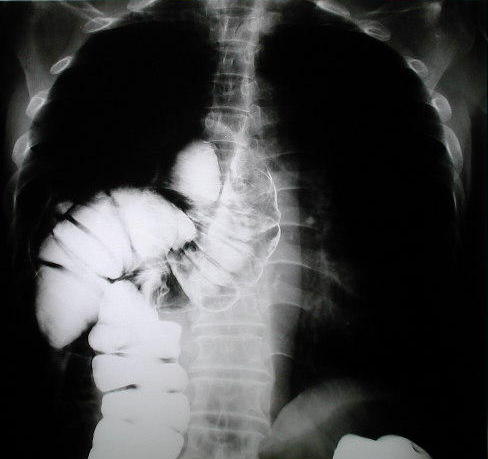

Colon por enema y técnica de doble contraste

Evidencia el contenido en el espacio del hemi tórax derecho y área mediastinal inferior, imagen densa, bien limitada, con austraciones, (contraste digestivo), en relación al colon ascendente, condicionando compresión extrínseca, anillo o brecha diafragmática, en seno costo diafragmático  y borramiento de la linea diafragmática derecha que confirma la presencia de hernia diafragmática derecha.

También puede observarse la hiperplasia compensatoria del pulmón Izquierdo.

Radiologia del tórax con contraste digestivo,